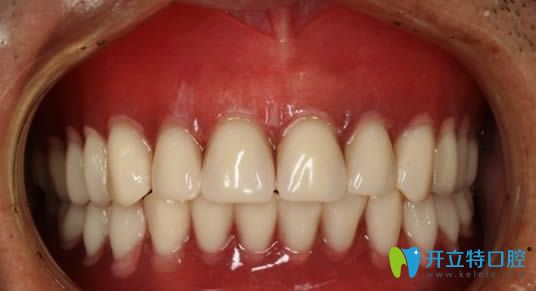

在杭州美奧口腔做完全口即刻種植牙后的照片

杭州美奧口腔的醫(yī)生說(shuō),我這種情況屬于高難度種植,一般牙科是無(wú)法種牙的,就這樣我懷著期盼的心在杭州美奧做了全口即刻種植牙。

在這里提醒大家,若條件允許,請(qǐng)優(yōu)先考慮種植牙而非活動(dòng)假牙。我個(gè)人體驗(yàn)到種植牙的咀嚼功能幾乎與真牙無(wú)異,它對(duì)日常飲食的影響極大。因此,希望大家不要因?yàn)閮r(jià)格因素而將就,畢竟種植牙的高性價(jià)比是不容忽視的。